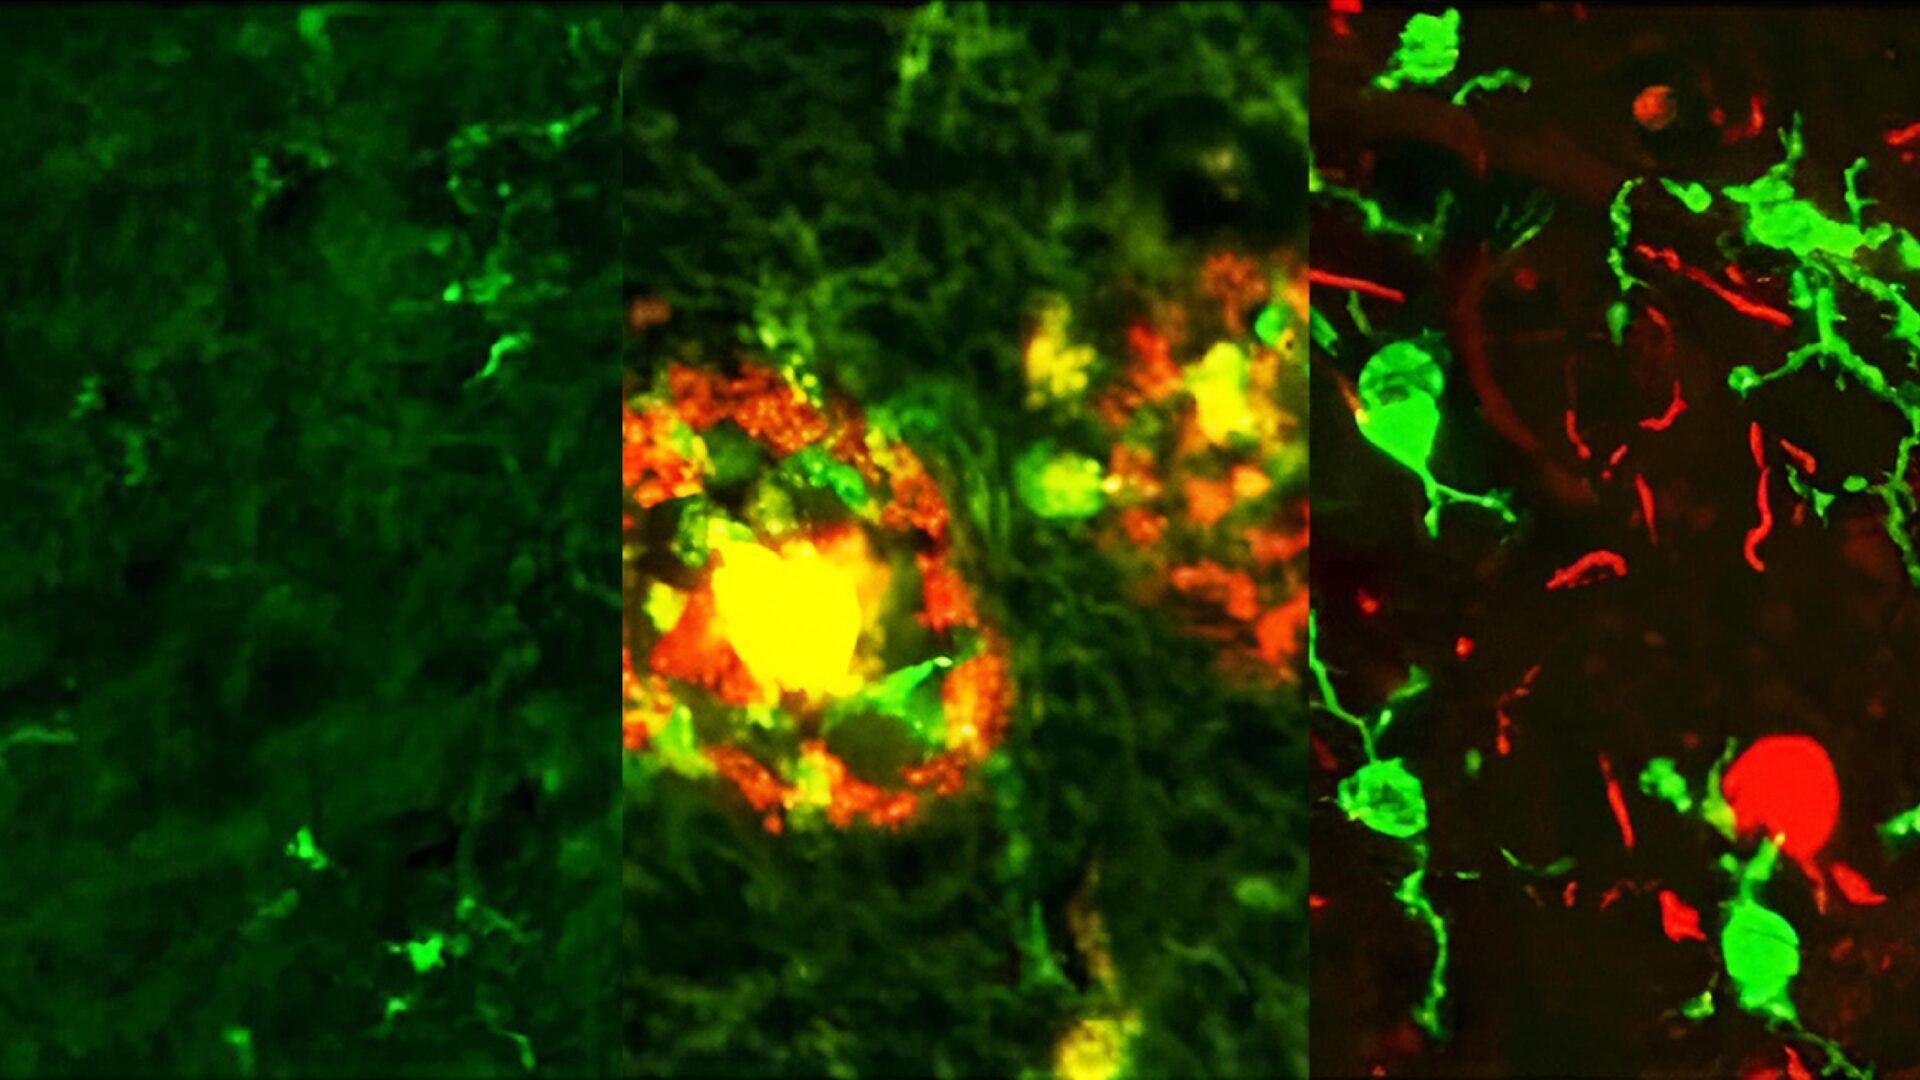

さらに、2023年8月に政府が提唱した「認知症・脳神経疾患研究開発イニシアティブ」を受け、ムーンショット目標7の枠組みのもと、認知症克服を目的とした新たな研究が加速しています。2024年11月からは、「脳内セノインフラメーション」を含む3件の新規プロジェクトが本格的に始動しました。